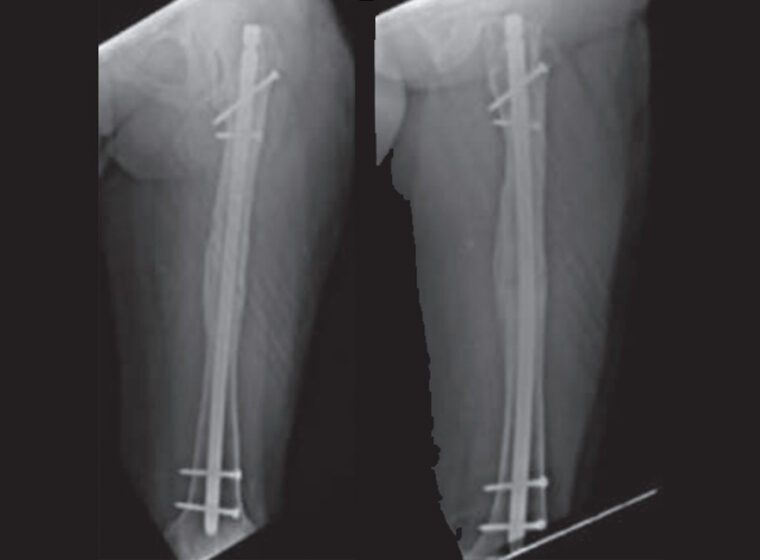

Ortobiológicos y aloinjertos en pseudoartrosis con pérdida ósea diafisaria femoral

Protocolos efectivos para pseudoartrosis refractaria de húmero mediante injerto tricortical e instrumentalación especializada